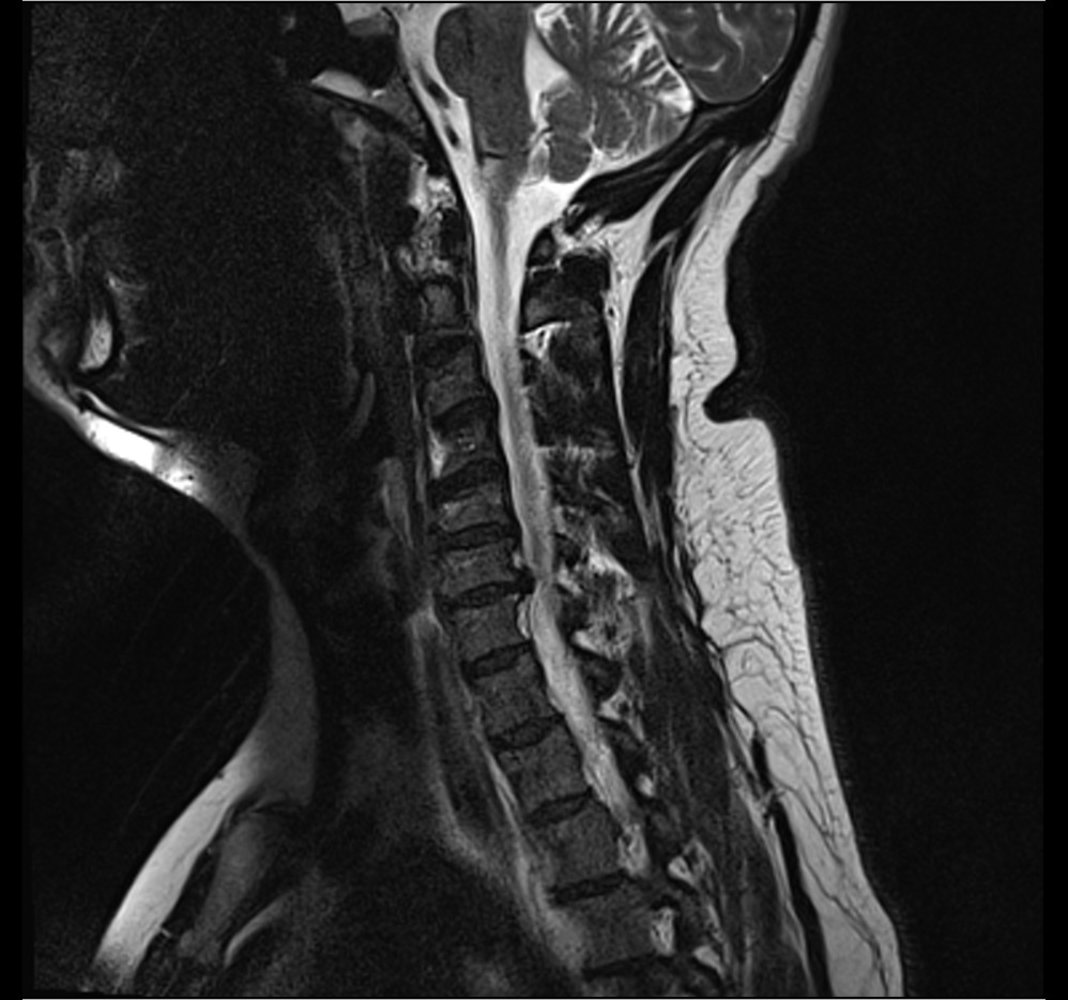

• MRI of the spine (imaging modality of choice) : determines the site of narrowing of the medulla and the underlying pathology

• Myelography (possibly with CT): if MRI is contraindicated (e.g., in patients with metal implants)